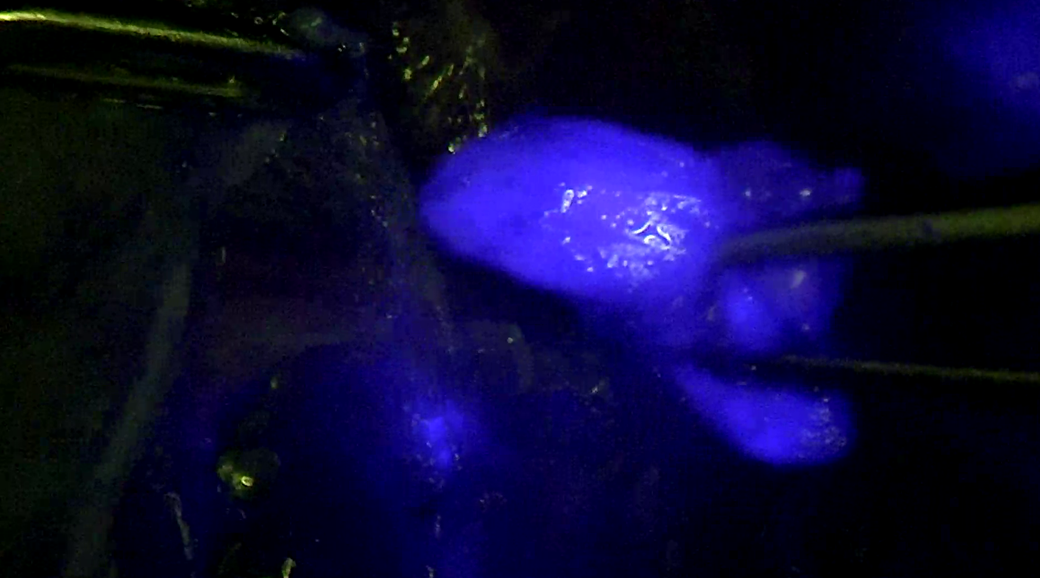

Στην Κλινική ΡΕΑ ασθενής με καρκίνο του ενδομητρίου υποβλήθηκε σε λαπαροσκοπική υστερεκτομή και διεγχειρητική ανίχνευση του φρουρού λεμφαδένα (SLN biopsy) με τη χρήση τελευταίας τεχνολογίας κάμερας (NIR/ICG) με τη βοήθεια της οποίας ο λεμφαδένας απεικονίζεται χρωματισμένος (εικόνες).

Επιπλέον με τη χρήση της ειδικής λαπαροσκοπικής κάμερας και χρωστικής ICG θα μπορούμε ενδεχομένως στο μέλλον να εντοπίζουμε το φρουρό λεμφαδένα με μεγάλη ακρίβεια με σκοπό τη μείωση της νοσηρότητας που μπορεί να προκύπτει από μία συστηματική λεμφαδενεκτομή.